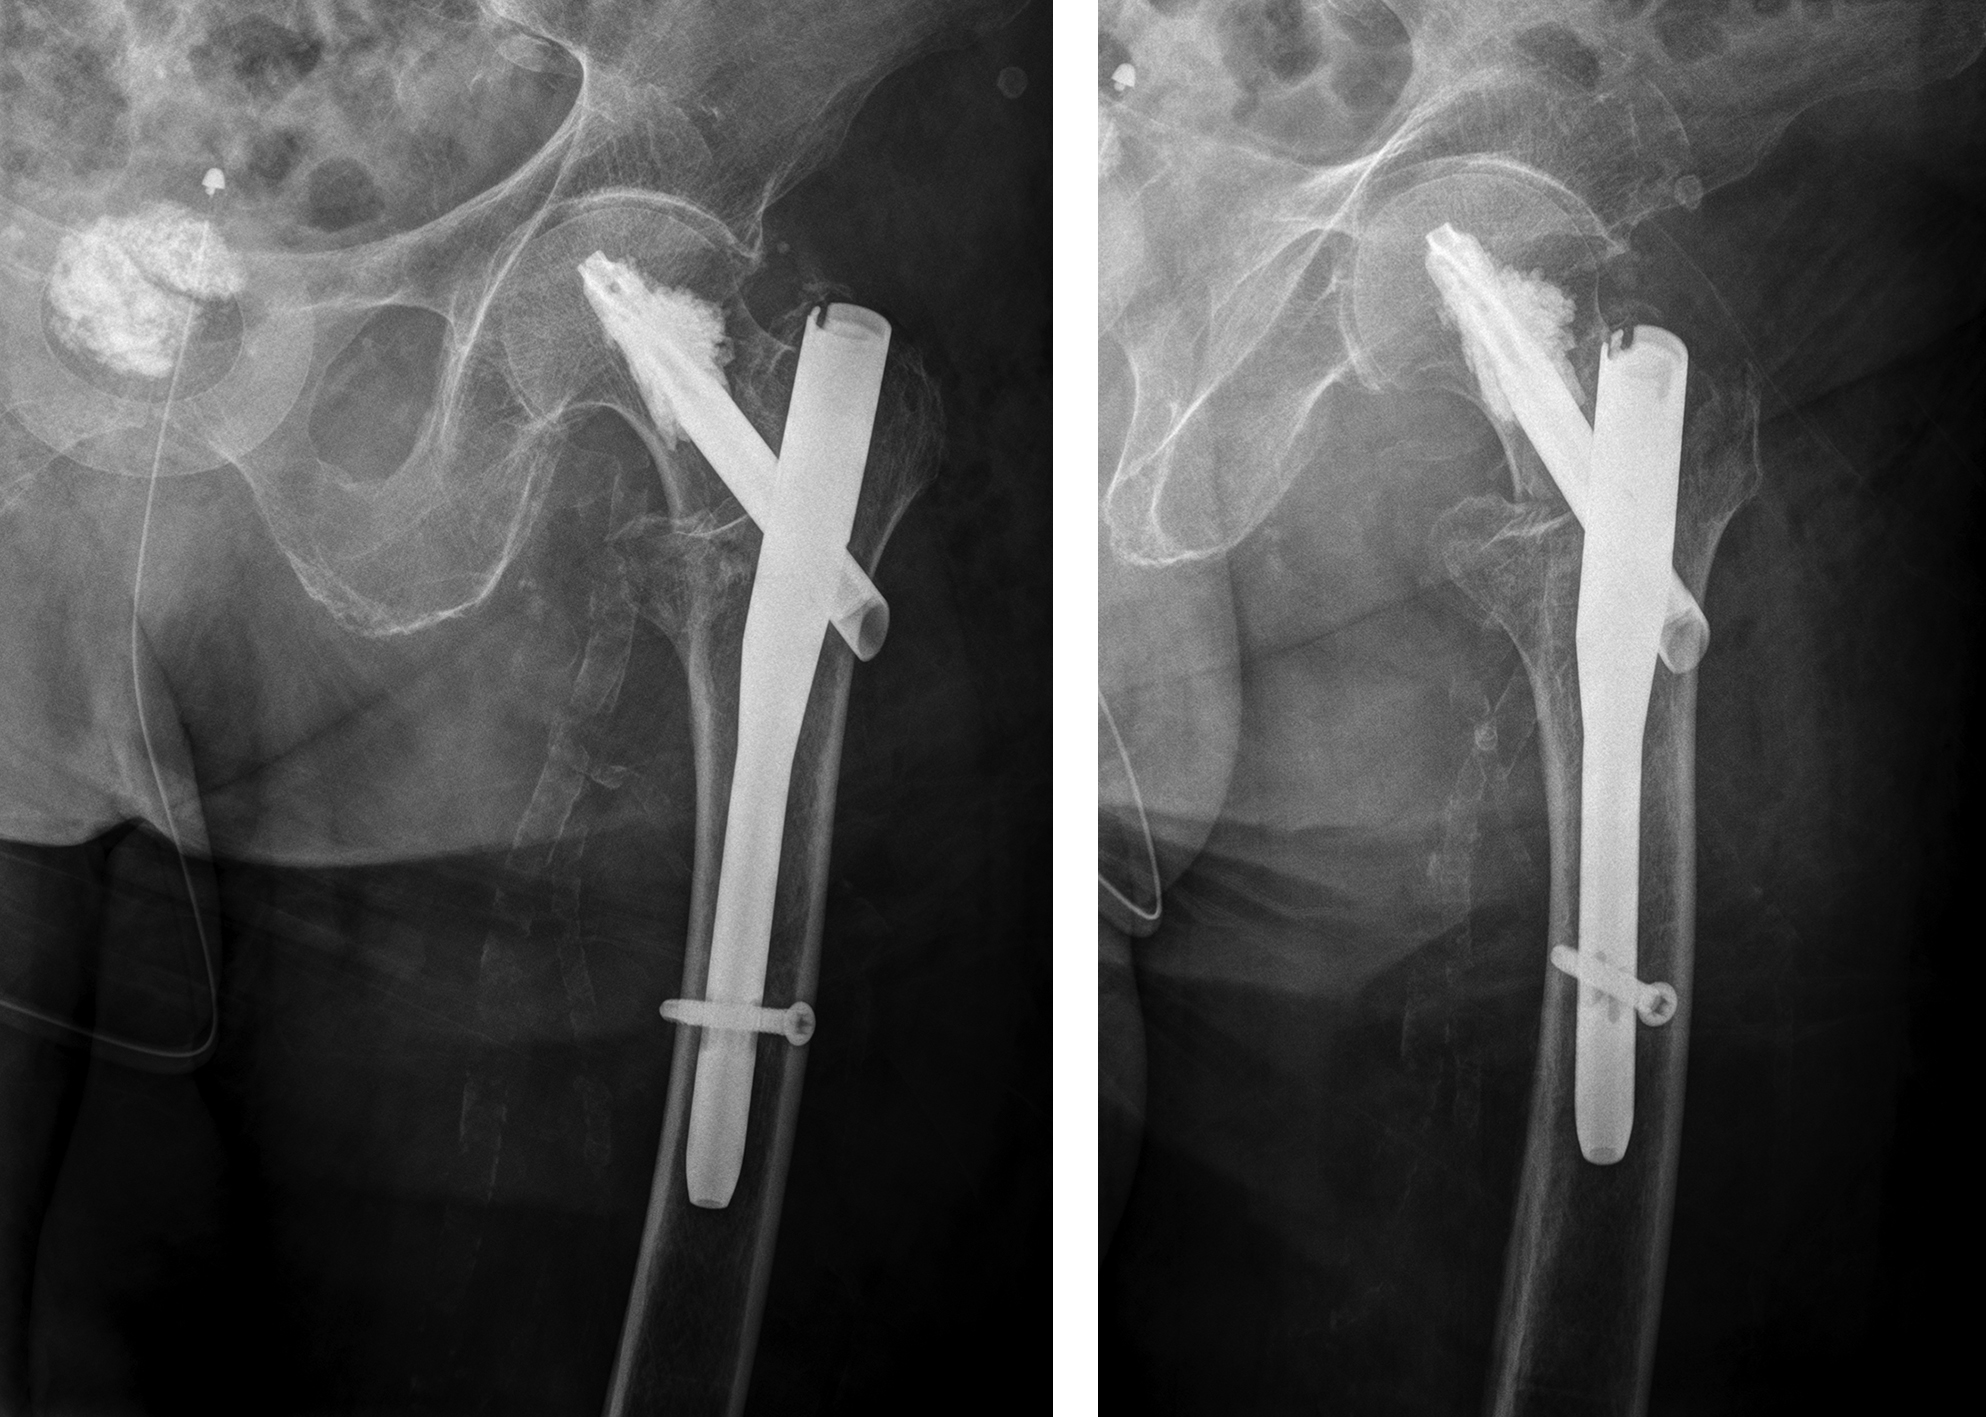

An 83-year-old female patient sustained a 31-A.2.2 fracture of the right proximal femur after a fall at home (Figs 1-2). Intraoperative and postoperative images are shown (Figs 3-5).